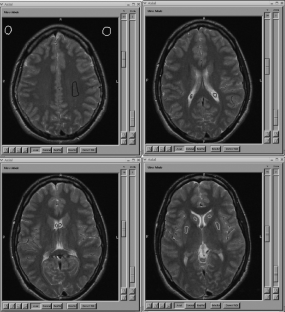

The ability to analyze and merge data across sites, vendors, and field strengths depends on one's ability to acquire images with the same image quality including image smoothness, signal-to-noise ratio (SNR) and contrast-to-noise ratio (CNR). SNR can be used to compare different magnetic resonance scanners as a measure of comparability between the systems. This study looks at the SNR and CNR ratios in structural fast spin-echo T2-weighted scans acquired in five individuals across ten sites that are part of Functional Imaging Research of Schizophrenia Testbed Biomedical Informatics Research Network (fBIRN). Different manufacturers, field strengths, gradient coils, and RF coils were used at these sites. The SNR of gray matter was fairly uniform (41.3–43.3) across scanners at 1.5 T. The higher field scanners produced images with significantly higher SNR values (44.5–108.7 at 3 T and 50.8 at 4 T). Similar results were obtained for CNR measurements between gray/white matter at 1.5 T (9.5–10.2), again increasing at higher fields (10.1–28.9 at 3 T and 10.9 at 4 T).